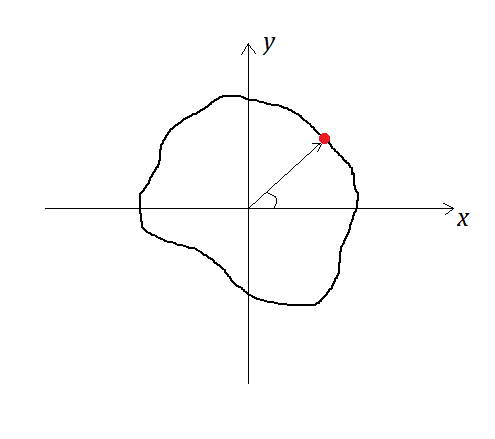

Suppose that and are matrices containing inner and outer contour points of the cardiac muscle at respectively and and are matrices containing inner and outer contour points at . Also assume that represents the coordinates of the center of gravity of inner contour at . With these assumptions the coordinates of all contour points, inner and outer, can be represented with respect to the center point. In other words, for simplicity, the position of the center of gravity can be assumed fixed and the contour points’ positions are represented with respect to the center point as the center of coordinate system. It should be mentioned that this assumption is only valid for deforming objects with small strain which is the case of analysis in cardiac modeling. Also the cardiac muscle deformation is a radial deformation and this assumption is not valid for non-radial deformations. This assumption can lead to increased error in the deformation analysis of non-convex objects.

Based on the above mentioned notes, the displacement vectors can be computed in the following order:

-

1.

The center of gravity of the inner contour points is computed and assumed fixed from time to time .

-

2.

In accordance with the center, contour points can be ordered based on the angle of the crossing line between the point and the center and horizontal axis. Fig. 1 shows the procedure.

-

3.

After ordering all the contour points, the displacement vectors for corresponding points between two time steps (the points with the same angle) can be computed.